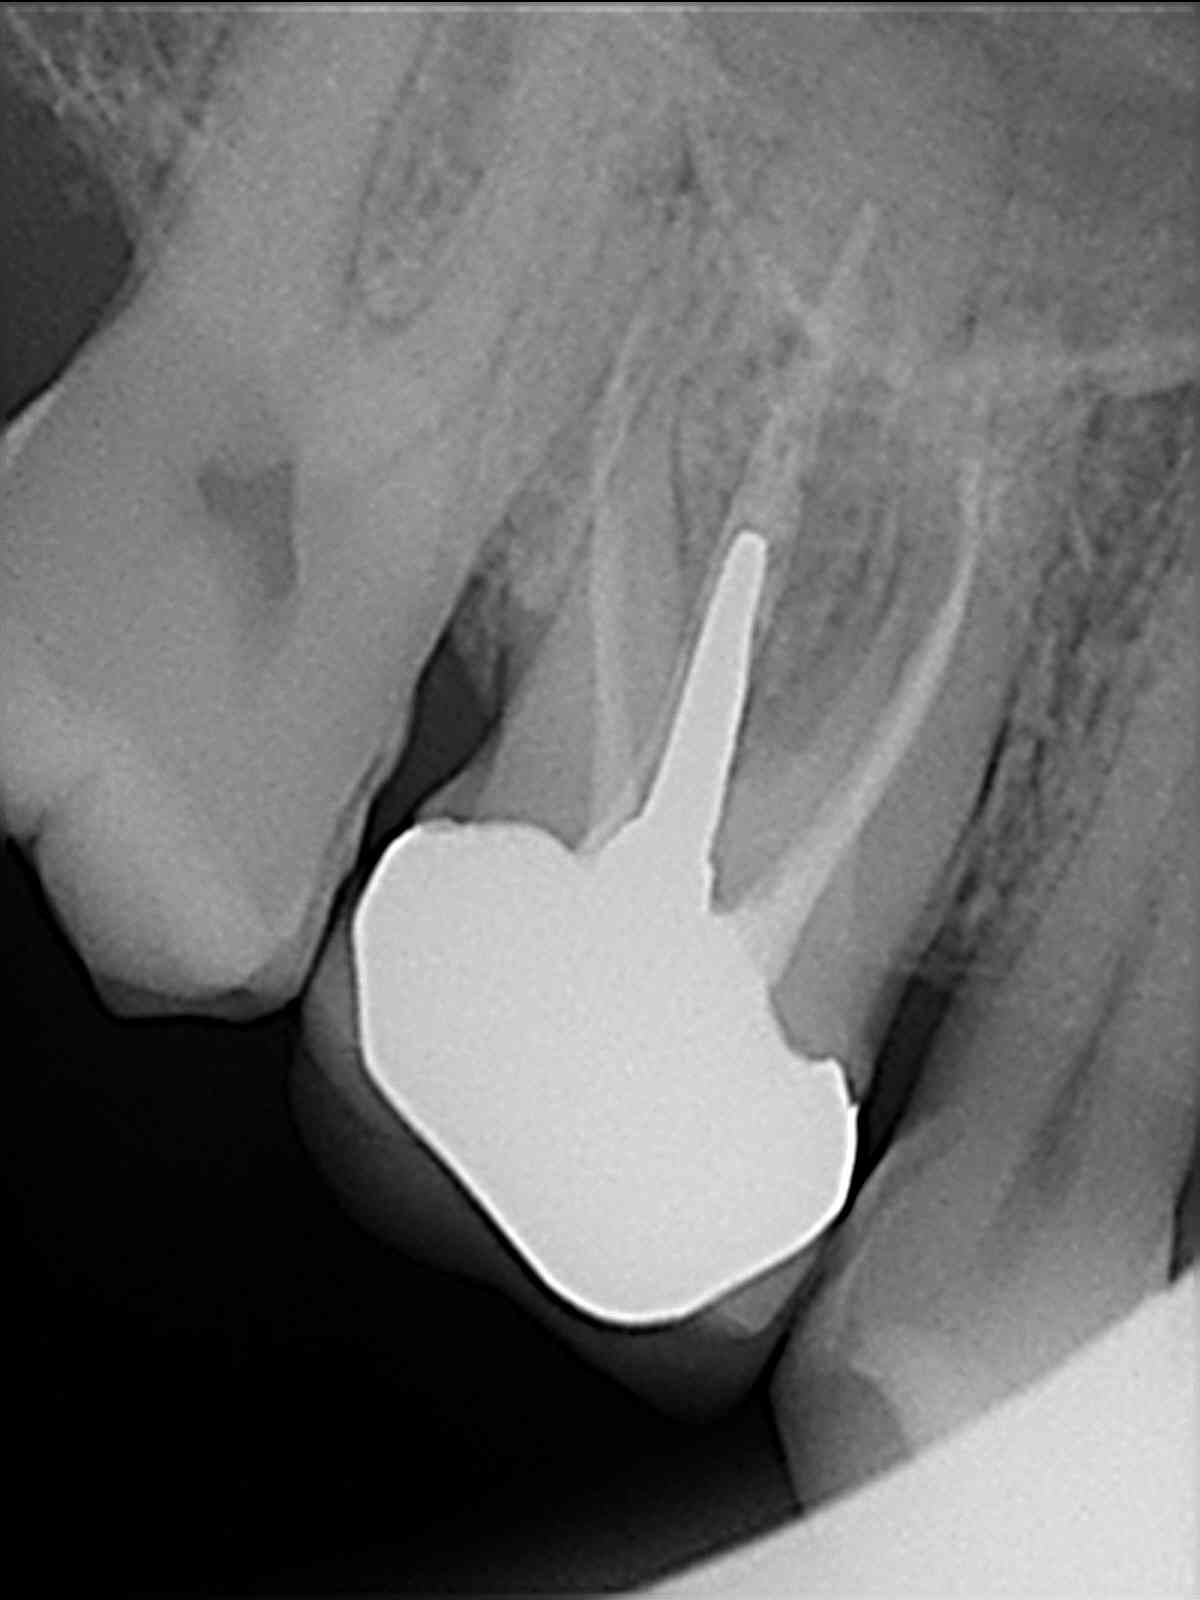

Sinds afgelopen woensdagochtend heb ik vreselijke pijn onder een kroon (de1.6). Op de foto (zie bijlage) is geen ontsteking te zien volgens de tandarts. Naar huis gestuurd met amoxicilline/Clavulaanzuur 500 en Ibuprofen 600 mg + paracetamol + codeine. Pijn wordt steeds erger ipv minder... Tandarts zegt dat er waarschijnlijk een breuk in de wortel zit omdat er aan de achterkant van de kies een pocket zit van wel 10mm diep. Daar komt ook pus uit. Kan kies nu niet trekken zegt hij omdat verdoving door de ontsteking niet zou werken. Ontsteking moet eerst weg, daarna trekken en implantaat plus nieuwe kroon erop.